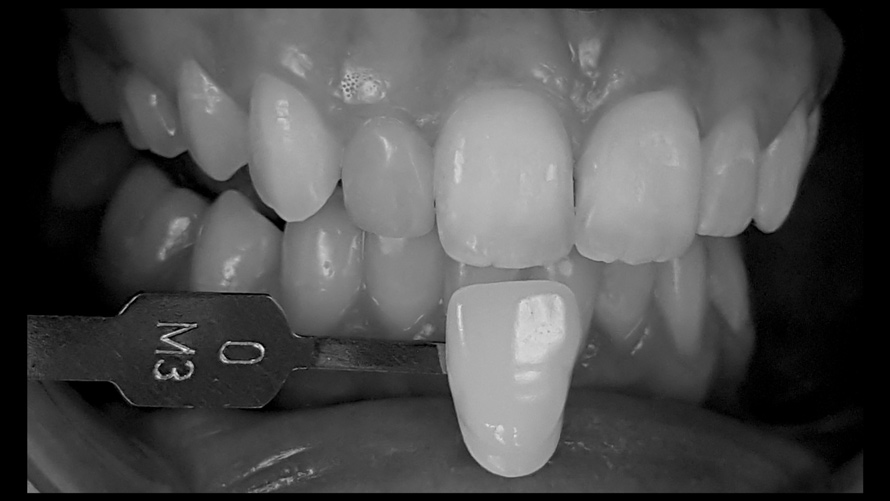

(18.) Tooth shade analysis of value, chroma, and hue taken with a smartphone and an EALS device.

Figure 18

(19.) Tooth shade analysis of value, chroma, and hue taken with a smartphone and an EALS device.

Figure 19